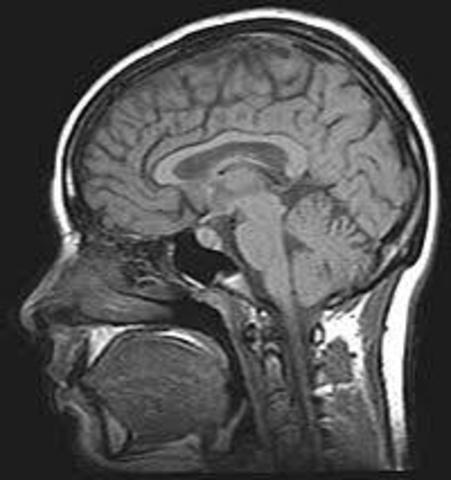

• Resonancia nuclear magnética

Resonancia nuclear magnética

Se obtiene la primera Resonancia Nuclear Magnética de un ratón.